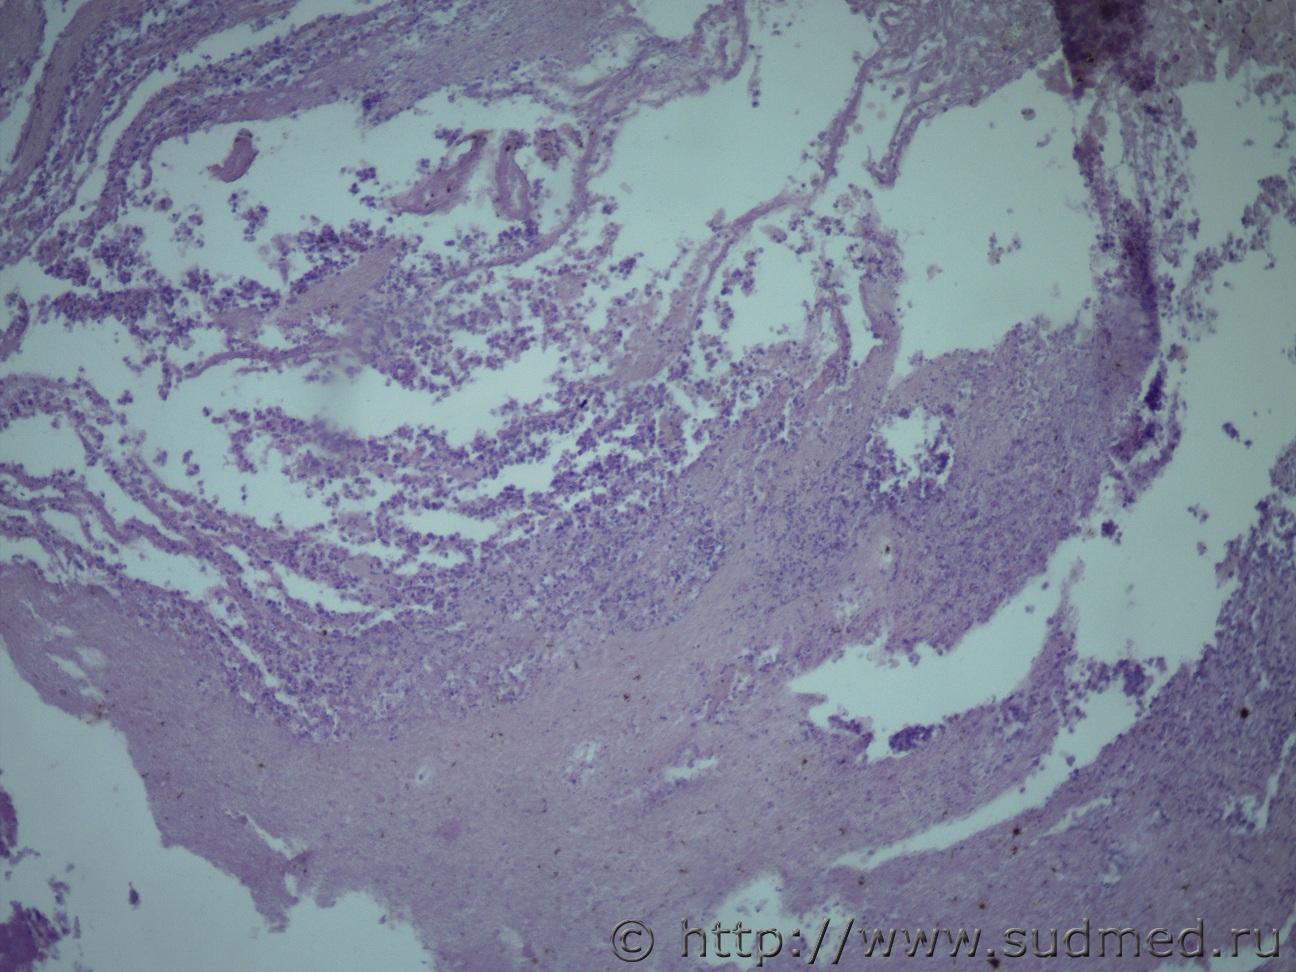

Добрый день! Ув. коллеги, нужна ваша помощь. Головной мозг жен. 28 лет. 1 год в коме после остановки сердца в послеоперационном периоде. Под микроскопом тотальный некроз головного мозга. Грибковый энцефалит?Судебная медицина - Прикрепленное изображение Судебная медицина - Прикрепленное изображениеСудебная медицина - Прикрепленное изображениеСудебная медицина - Прикрепленное изображениеСудебная медицина - Прикрепленное изображение

Похожи на криптококки, особенно на 9 фото.

Мое мнение за лейкомаляцию

Что это за клетки на фото ?

Ув.Медик! Это микроглиальные клетки (d=длиной 6мкм, шириной 3-4 мкм) и они выполняют в ГЭБ, ЛЭБ, ГЭБ местную иммунно-защитную роль, при повреждении субстрата г/м подвергаются ишемии и трансформируются в глиально-макрофагальные с дегрануляцией и набухшие с кариорексисом , кариолизисом и ядерными детритами. Криптоподобные округлые клетки- это амиободный фенотип микрглии играющие фагоцитарную функцию при длительной ишемии.А пигментные - это липофусцины.